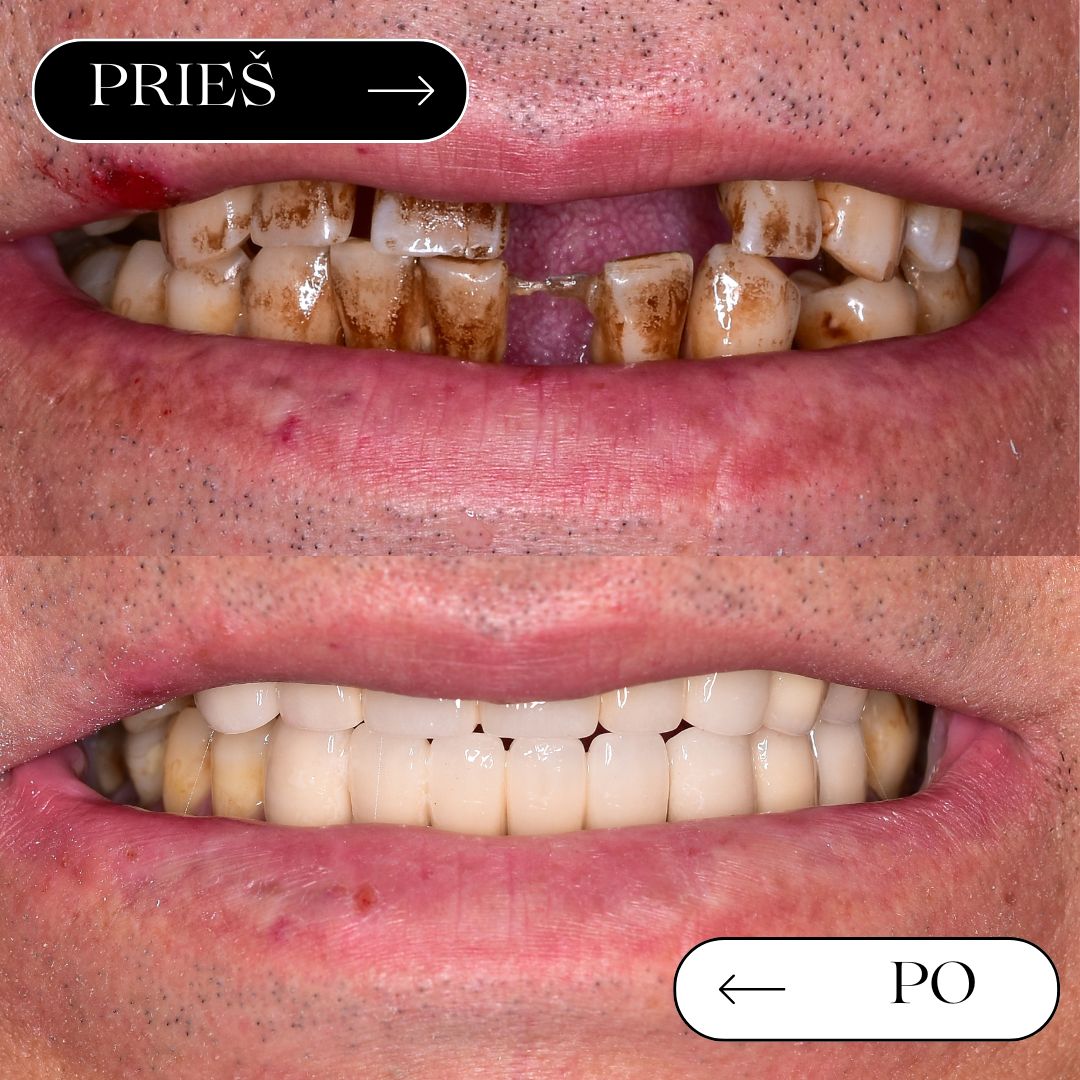

Prieš / po

rezultatai

Geriausias įrodymas – realūs pacientų pokyčiai. Atkurta estetika ir funkcija gali leisti vėl šypsotis be baimės.

Abiejų žandikaulių atkūrimas